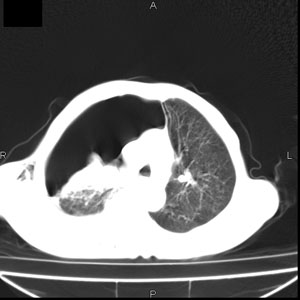

患者男,77岁,于3日前从树上摔下,头部查ct示蛛血,硬膜下出血,上腹部ct未见明显异常,右侧胸腔积液,左侧如常。肺部拍片示右侧肋骨多发骨折住院后今日来查肺部ct,我看到的是1。右侧胸腔血气胸并右肺上叶,中叶压缩性肺不张,2。右肺下叶肺挫伤并多发肋骨骨折,肌内及皮下积气3。左侧少量胸腔积液,我想请教的是3天前左侧胸腔里没有积液今天怎么出现了呢,是什么原因呢?请讨论。

有肺挫裂伤,有渗出,

回复楼主   左侧液气胸,液体来源1、肯定有血液成分,多少不一定。2、胸膜腔渗液,由于肺压缩、活动度下降,肯定胸膜吸收有问题,导致积液增多。

因为3天前病人刚摔的时候,左侧胸腔受伤不严重,故而当时没有胸腔积液,但病人受到这么大的伤害,胸膜腔内的液体动态平衡肯定会受到影响,所以过一段时间后才出现胸腔积液。